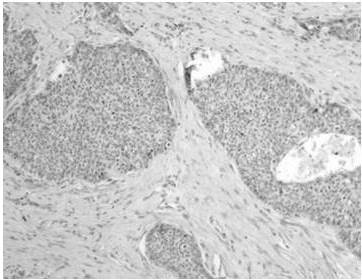

En la reclasificación los casos de ADC estuvieron representados por: ADC patrón predominantemente sólido 57,3 % (Figura 3 y 4), ADC patrón acinar 18,2 % (Figura 5) y en menor frecuencia ADC con patrones mixtos como: patrón predominantemente sólido y acinar 3,6 %, ADC patrón predominante sólido con células en anillo de sello 2,7 %, ADC patrón predominante acinar y micropapilar (Figura 6), patrón predominantemente acinar y sólido, papilar y acinar y patrón predominantemente papilar (Figura 7) cada uno con 1,8 %, asimismo, se encontraron en menor cantidad los siguientes patrones: lepídico no mucinoso (Figura 8) tipo intestinal (Figura 9), mucinoso (Figura 10), y otros patrones mixtos con 0,9 % cada uno (Cuadro 4)

Al reclasificar los casos de ADC de pulmón se encontró el patrón predominantemente sólido 57,3 % como el más común en segundo lugar el ADC patrón acinar 18,2 % y en menor frecuencia: ADC patrón predominantemente sólido y acinar 3,6 %, ADC patrón predominante sólido con células en anillo de sello 2,7 %, ADC patrón predominante papilar, otros patrones mixtos y tipos menos frecuentes. Esto se asemeja a lo encontrado Tsao y col. (10) en el estudio LACE-Bio el cual es el estudio de cohorte multinstitucional más grande hasta el momento en el que se reclasificaron 575 casos de ADC de pulmón para predecir el beneficio de la quimioterapia adyuvante en pacientes sometidos a resección completa obteniendo de igual forma el subtipo predominantemente sólido como el más común con 46 % seguido en secuencia del subtipo predominantemente acinar 26 % siendo este primero equivalente a carcinomas pobremente diferenciados sin ninguna característica de diferenciación reconocible morfológicamente y determinando un peor pronóstico para el subtipo sólido y micropapilar (semejante a lo observado en mama) con una supervivencia más baja y respuesta pobre al tratamiento (10) . De forma similar Warth y col. (19) reclasificaron 100 casos de ADC pulmonares con el fin de determinar la variabilidad inter-observador de la clasificación propuesta por IASLC / ATS / ERS para los ADC pulmonares obteniendo de igual manera el subtipo predominantemente sólido como el más frecuente (37 %), seguido de acinar (35 %), lepídico (20 %), papilar (5 %) y micropapilar (3 %) este resultado de igual forma se asemeja al nuestro con una población similar. Análogo a nuestro resultado también Warth y col. (20) realizan otro trabajo de investigación reclasificando 40 casos de ADC pulmonar con el propósito de determinar la concordancia teniendo en cuenta la nueva clasificación y encontró el subtipo predominantemente sólido, más frecuente con mayor nivel de concordancia.